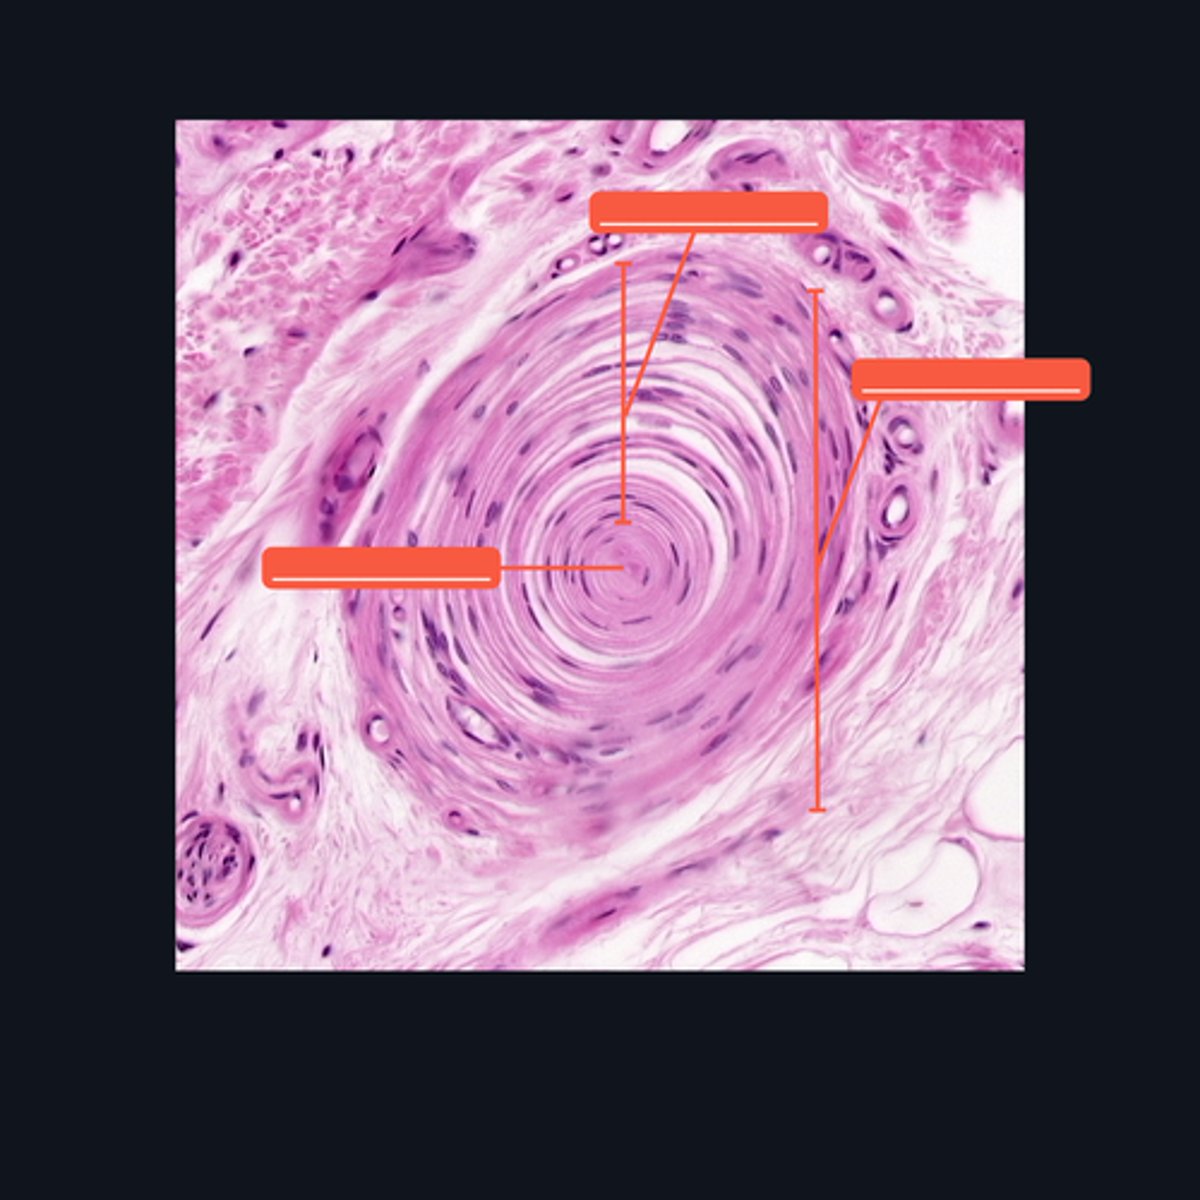

Peripheral Nerve

Identify where this structure is found

(top 3) from left to right

Perineurium

Axon

Myelin sheath

(bottom 2) from left to right

Endoneurium

Schwann cell

Identify the pointed structures.

Peripheral Nerve

Identify the structure on the image.

(top to bottom)

Axon

Endoneurium

Myelin sheath

Identify the pointed structures.